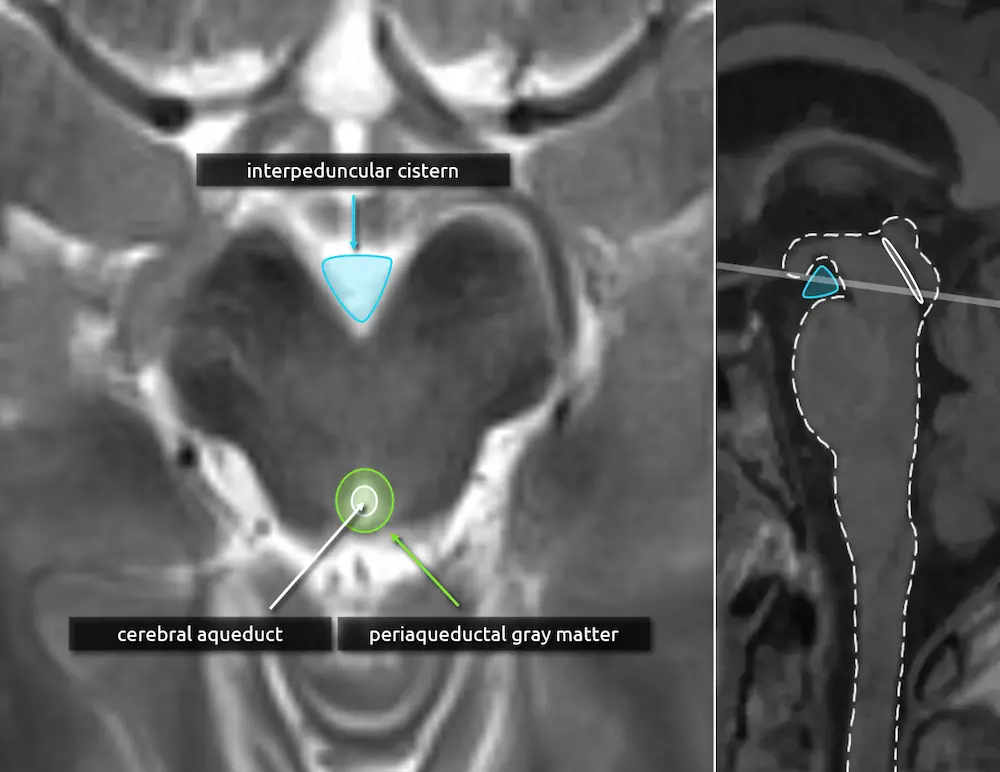

The midbrain in axial cross section has a "Mickey Mouse" appearance, most obvious in the rostral (upper) part.

1. Interpeduncular cistern

The interpeduncular cistern is the triangular CSF space located between the ears of the "Mickey Mouse." When a patient is lying flat on their back, like during a brain MRI, it is a dependent position and may collect small volume subarachnoid hemorrhage.

2. Cerebral aqueduct

The cerebral aqueduct (of Sylvius) is a thin CSF channel that courses through the midbrain, connecting the third and fourth ventricles. Stenosis of the cerebral aqueduct is the most common cause of congenital hydrocephalus.

3. Periaqueductal gray matter (see below)

3. Periaqueductal gray matter

The periaqueductal gray matter is a rim of gray matter surrounding the cerebral aqueduct. Abnormal signal intensity here is common and nonspecific but classically is a feature of Wernicke encephalopathy.